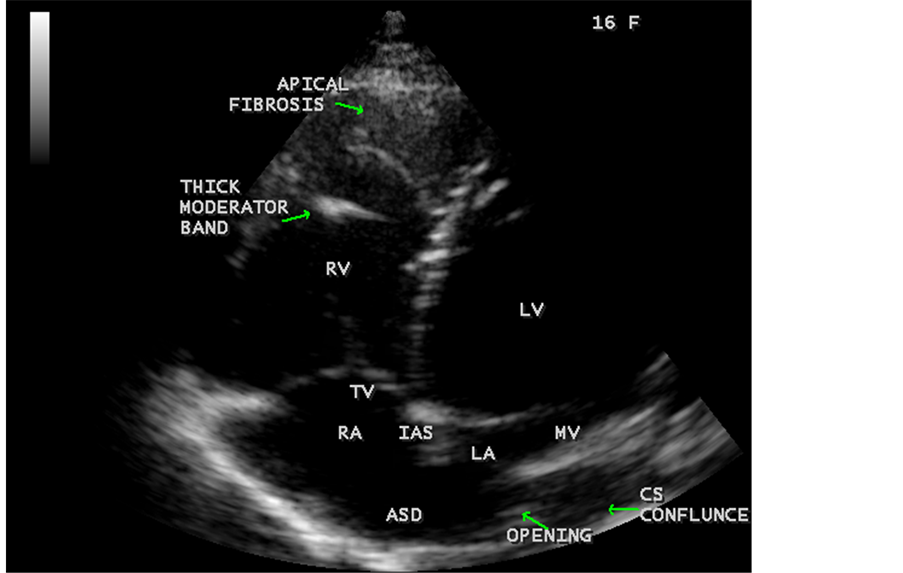

Figure 46. Showing RV EMF with fibrosed and thickenned moderator band in a 16-year-old female in cardiac type TAPVC (total anomalous pulmonary venous connection) with ASD (atrial septal defect).

ventricle”) in a 16-year-old female as shown in Figure 50 to Figure 53 were detected. RV EMF with rheumatic involvement of mitral valve as shown in Figure 54 and Figure 55 in a 44-year-old female and in Figure 63 in a 55-year old female. Biatrial enlargement due to rheumatic atrioventricular (AV) valves (mitral and tricuspid) involvement characterized by stenosis of the valves are illustrated in Figure 56 to Figure 59 in a 54-year-old female and it is differentiated from EMF which is characterized by AV valve regurgitation as shown in Figure 34 and Figure 60. RV EMF associated with thickening and fibrosis of moderator band in a 16-year-old female was shown in Figure 46. RV EMF associated with apical left ventricular hypertrophic cardiomyopathy was shown in a 47-year-old male as in Figure 61 and in a 65-year-old female as in Figure 62.